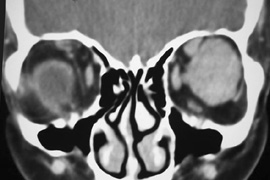

Fig. 16. A. Patient with right orbital cellulitis. B. Coronal CT scan demonstrating subperiosteal abscess formation from frontal and ethmoidal sinusitis. C. Frontoethmoidal orbitotomy incision marked for abscess drainage.

The periosteum is exposed and incised with a Freer elevator and then is reflected off the bone posteriorly. It is generally quite adherent to the curved contour of the medial canthal bones, especially at the medial canthal tendon. The anterior lacrimal crest is encountered inferiorly. Care should be taken not to damage the lacrimal sac with the elevator. The posterior lacrimal crest is visible behind the sac. Adequate mobilization of the periosteal connections to the anterior lacrimal crest gives a large area of exposure. The periosteal elevation is carried superiorly in the area of the trochlea. Elevation of the periosteum opens the subperiosteal space. Blood or pus caused by fracture or infection, if present in this space, is encountered at this point.

Elevation of the periorbita along the medial orbital wall posterior to the lacrimal sac progresses easily. Orbital fractures involving the thin ethmoid bone are seen at this point. The anterior ethmoidal artery is seen at the junction of the ethmoidal and frontal bones where the orbital roof meets the medial orbital wall (see Fig. 7). Usually it is found on a line extending posteriorly from the superior border of the medial canthal tendon. This artery either should be thoroughly cauterized with the bipolar cautery or clipped with a vascular clip before cutting. As the dissection in the subperiosteal space moves posteriorly, the orbit narrows. The posterior ethmoidal artery is identified. This is a reliable landmark for the optic foramen, which lies approximately 5 mm behind the ethmoidal artery.

Indications

The frontoethmoidal medial orbitotomy allows access for a variety of procedures in the subperiosteal and peripheral surgical spaces and sinuses (Fig. 17). Its main use is for processes involving both the frontal or ethmoid sinuses and the orbit. Entrance into the subperiosteal space is obtained easily. Drainage of subperiosteal blood or pus occurs as the space is entered.

Fig. 17. Schematic demonstration of areas amenable to frontoethmoidal orbitotomy. Coronal (A) and axial (B) views. This approach can be used for exposure of the medial orbit, ethmoid and sphenoid sinuses, and optic canal.